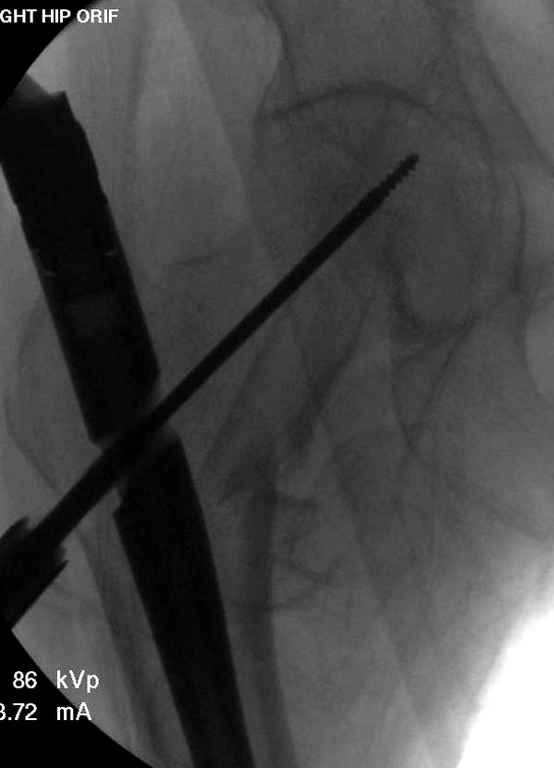

С приходом менее агрессивных блокируемых цефаломедуллярных гвоздей (Gamma 3 и другие) изменилась тактика лечения. Несмотря на то, что вся стабильность держится вокруг одного блокирующего винта, в большинстве случаев гвозди приводили к успеху.

Вашему вниманию представляется похожий случай, пациентке 70, осложнился в течение одного месяца после операции. Ревизия с заменой сустава, кабельная фиксация на трохантер. При установке в дистальном диафизе обнаружен тонкий кортикальный слой и сделана профилактика от возможного перелома аллографтом.